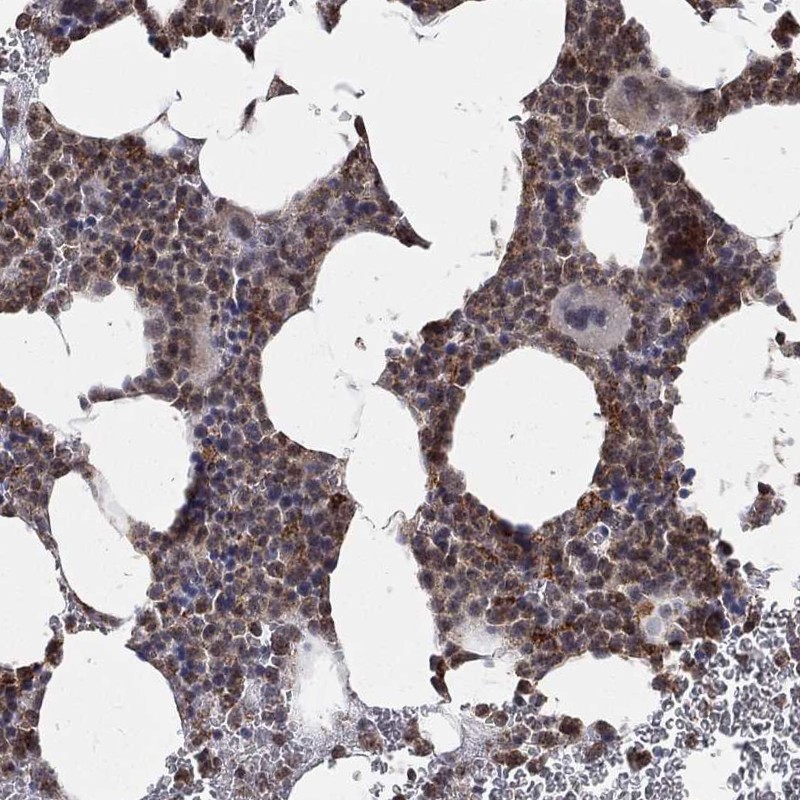

Immunohistochemical staining of human bone marrow shows strong cytoplasmic positivity with a granular pattern in hematopoietic cells.